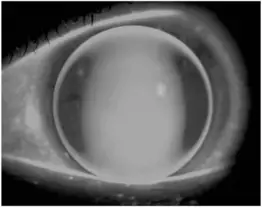

題目所附螢光染色圖片,以鈷藍光觀察,可見:

- 中央區域:明顯大面積亮帶(螢光池化,clearance),提示鏡片後弧較角膜陡,中央有淚液聚積

- 鏡片周邊:呈現一圈較亮的周邊邊緣弧帶

- 整體形狀:橢圓形偏向橫向(水平方向較寬),中央亮帶在水平方向延伸較廣

此圖型提示:鏡片對應水平方向角膜較陡(steep at horizontal),即**逆規角膜散光(against-the-rule astigmatism, ATR)**特徵——水平子午線為陡 K,垂直子午線為平 K,球面 RGP 在水平方向產生淚液池化(亮),垂直方向接觸承壓(暗),形成橫向螢光分布。